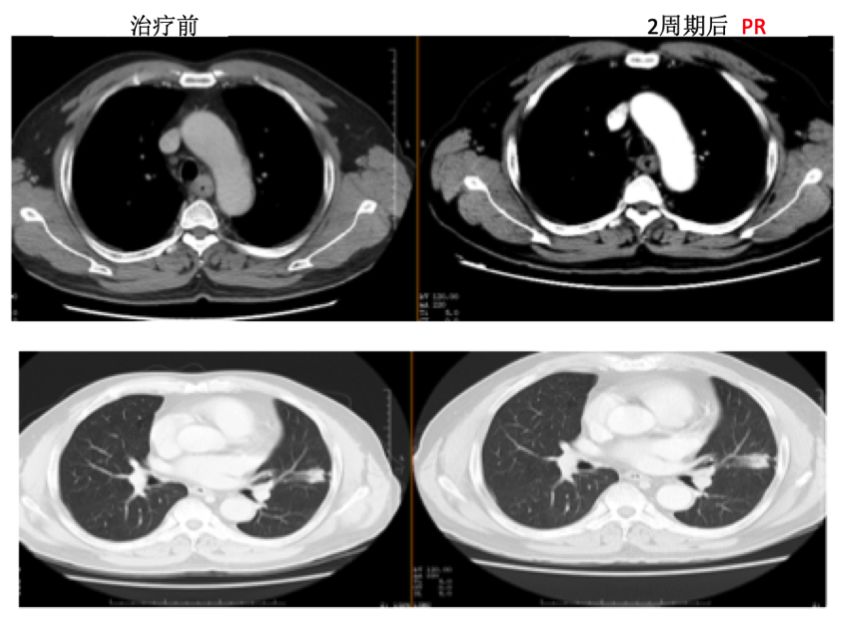

治疗后患者咳嗽减轻,吞咽困难明显缓解。查体:双颈部仍可触及多个肿大淋巴结,但较前明显缩小,最大约1cm×1cm,质硬,固定,无压痛。治疗2周期后复查胸部CT,疗效评估为PR。